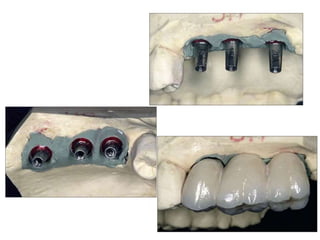

Implants require more precise impressions than crowns and bridges because implants lack a periodontal ligament to compensate for inaccuracies. It is critical to accurately record the three-dimensional position, angulation, and depth of implants to obtain a proper fitting definitive restoration. Making high quality impressions at the implant or abutment level is necessary to successfully fabricate implant prostheses.